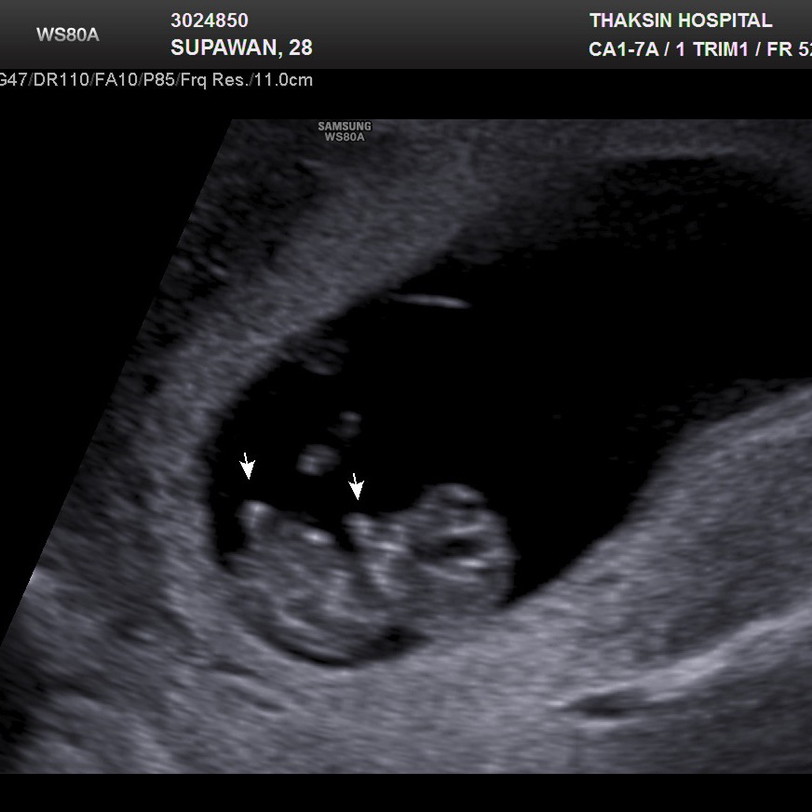

ในภาพ 13w5dคะ แต่น้องตัวโต